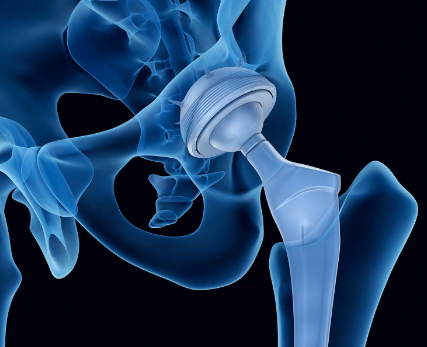

고관절 치환술(Total Hip Arthroplasty)

적응증: 고관절 치환술은 고관절 골관절염, 류마티스 관절염, 무혈성 괴사 또는 고관절 골절이 있는 개인에게 일반적으로 수행됩니다.

절차: 고관절 치환술 중 손상된 고관절의 볼-소켓 구성 요소를 인공 부품으로 교체합니다. 이 절차는 다양한 수술적 접근법을 사용하여 수행될 수 있습니다.

혜택: 고관절 치환술은 통증을 완화하고 고관절 기능을 회복하며 환자가 독립성과 이동성을 회복할 수 있도록 해줍니다.